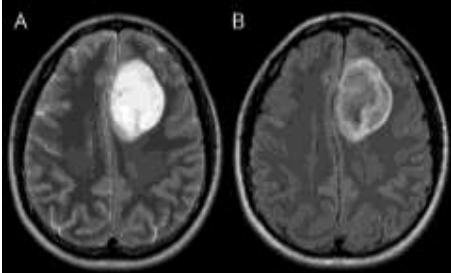

Durante a avaliação de uma ressonância magnética de um paciente com um tumor de origem glial recidivado (já diagnosticado por histopatologia), o radiologista se depara com o seguinte aspecto de imagem na avaliação das sequencias T2 e Flair.

Enunciado 3027976-1

Analise a importância do achado de imagem e assinale a alternativa correta.